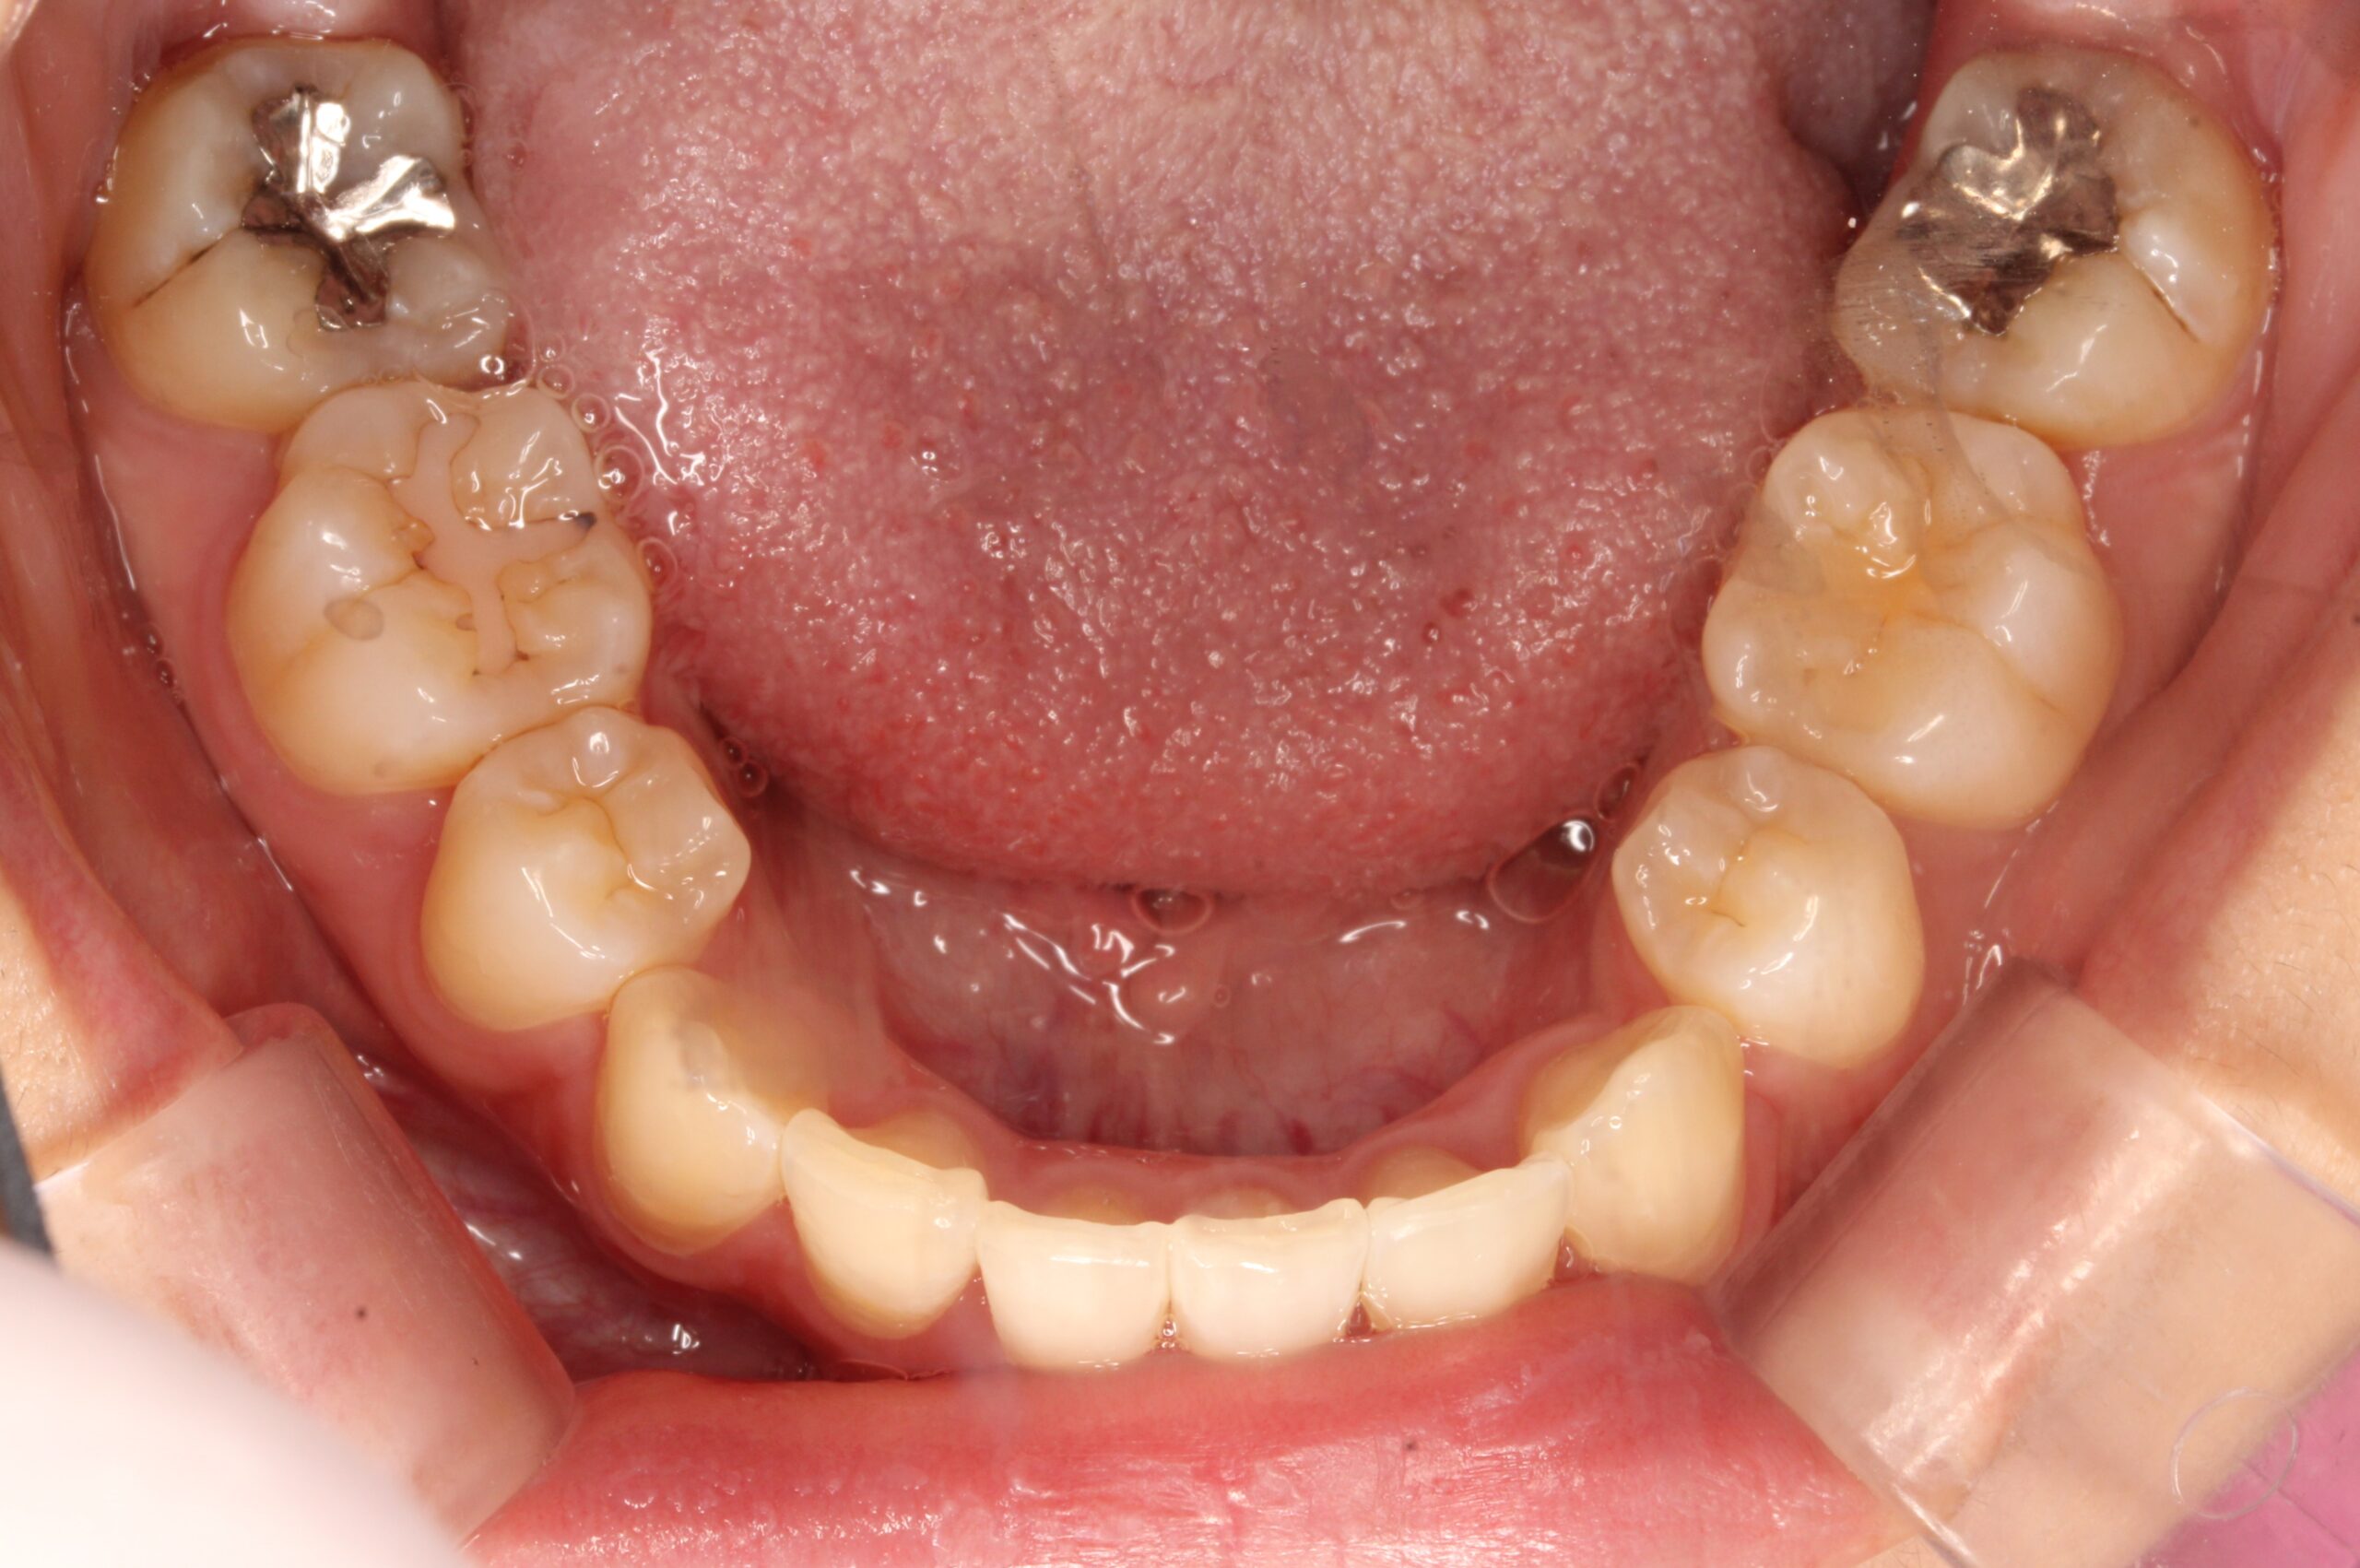

矯正術後:上顎

矯正術後:下顎